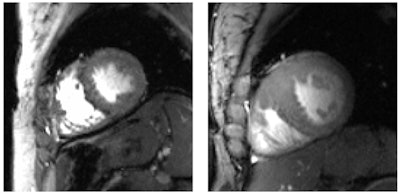

More specifically, 7-tesla MRI should have the unique ability to advance cardiac chamber quantification of the left and the right ventricles using high-density arrays of radiofrequency antennae. Several studies have reported an SNR increase with 7-tesla MRI of 2.1 times compared with 1.5-tesla. The enhanced uniform signal intensity creates high-quality images and high blood/myocardial contrast over the entire heart.

Ultrahigh-field cardiac MRI provides "an unprecedented potential for real-time imaging and addressing some of the shortcomings and physiological constraints of traditional assessments of left ventricular and right ventricular structure and function," noted the authors, citing "accelerated imaging capabilities of free-breathing real-time imaging" of the heart at 7 tesla.

In addition, 7-tesla MRI could advance myocardial tissue characterization through enhanced susceptibility effects. Such an outcome could be achieved by lowering the detection level for abnormal tissue compared with lower-field magnet strength and extending the dynamic range of sensitivity for monitoring T2-weighted changes, according to the authors.